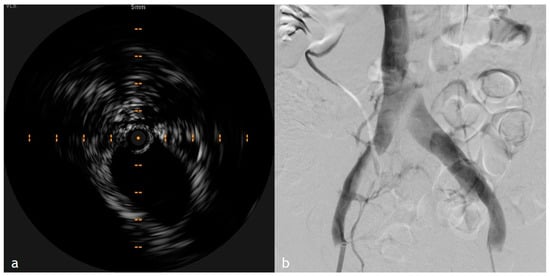

4. IVUS in PTS